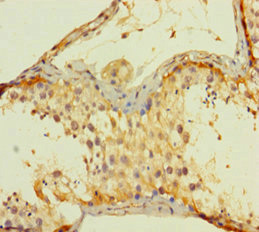

應用范圍:ELISA, IHC

Application Recommended Dilution IHC 1:20-1:200 -